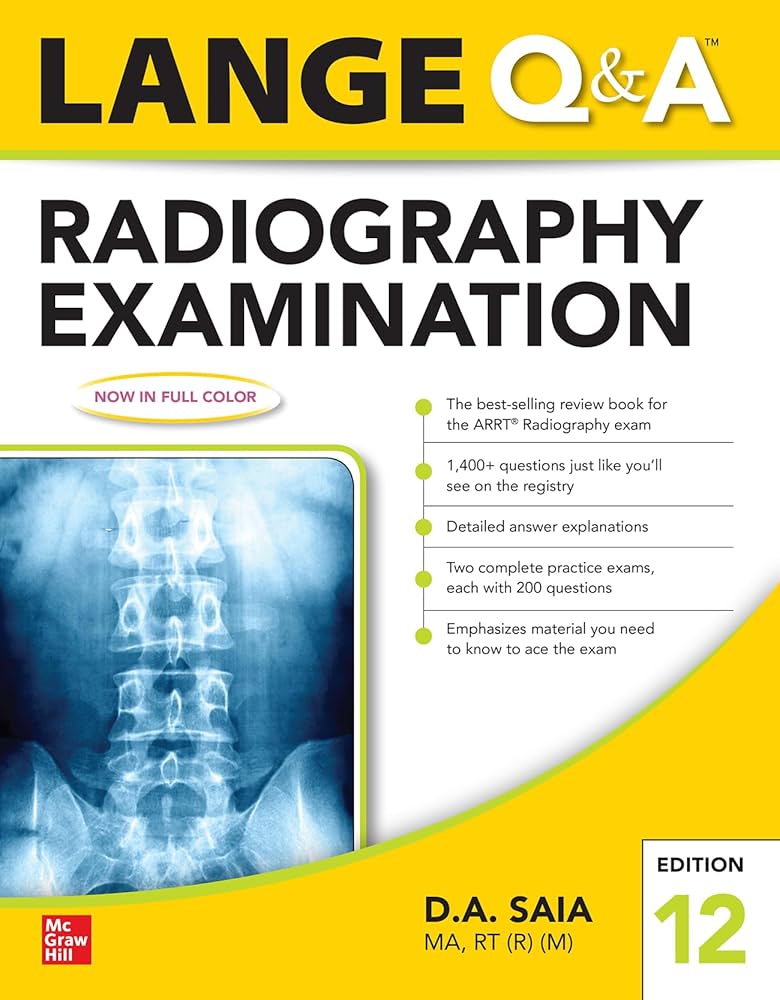

Arrt Radiography Mock Test Subscription, Passing the ARRT Radiography examination is a major milestone for aspiring radiologic technologists. The exam not only evaluates technical knowledge but also tests critical thinking, patient care understanding, and radiation safety awareness. With so much …

Arrt Exam Unlimited Mock Test Access, Preparing for the ARRT exam can feel overwhelming. With a vast syllabus, strict exam standards, and the pressure to perform well, candidates need a reliable and effective study strategy. One of the most powerful …

Arrt Exam Pro Mock Test Package, Preparing for the ARRT (American Registry of Radiologic Technologists) exam can be challenging. The exam not only tests your technical knowledge but also evaluates your ability to apply concepts in real clinical scenarios. This …